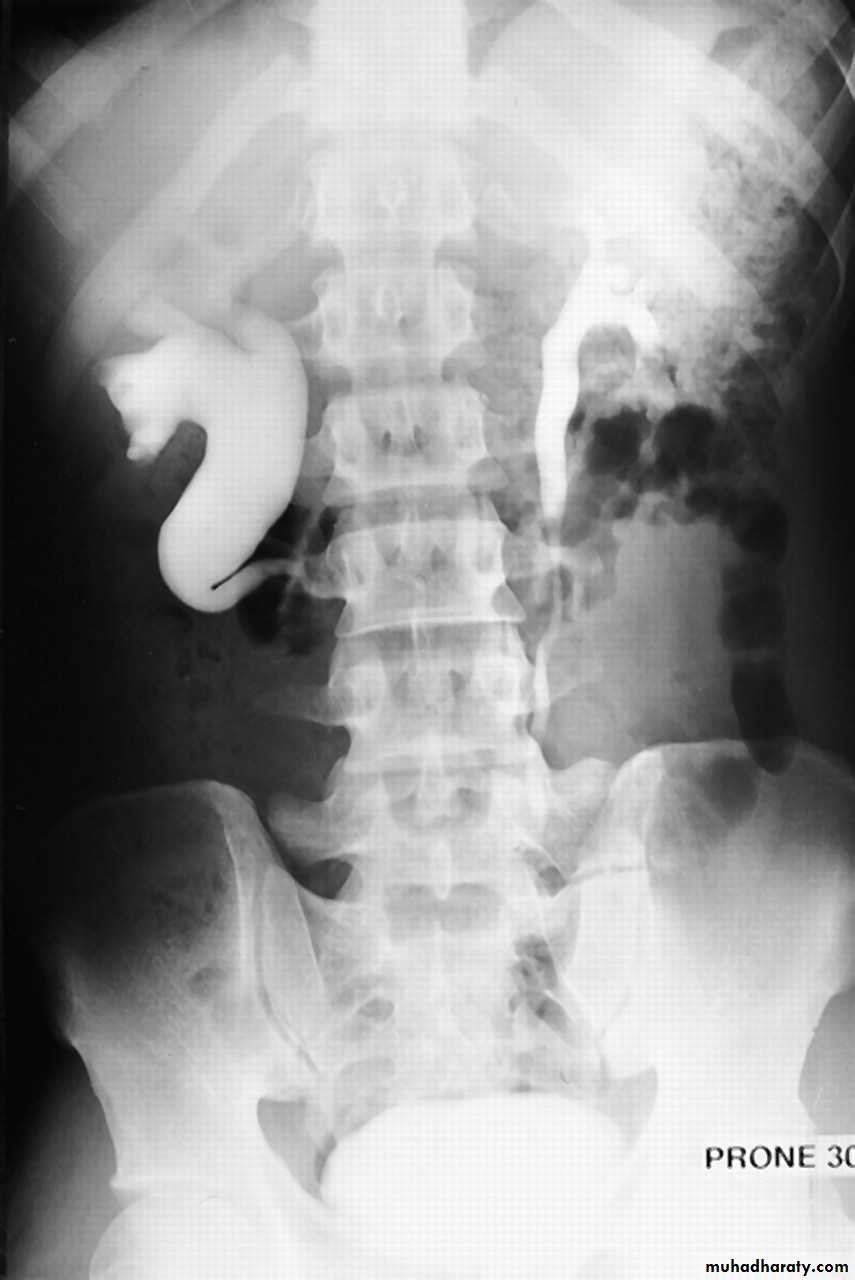

Horse shoe kidney -Kidneys may fail to separate.

-Almost invariably the lower poles remain fused.

-The kidneys axes are more parallel to the spine and malrotated.

-Diagnosis can be made by plain x-ray in some cases.

IVU shows

1. The kidneys at low position .

2.Close to the spine with long axis parallel to the spine .

3. Malrotation manifested by medially directed calyces.

4- The renal pelvis and ureters are anterior and lateral in position .